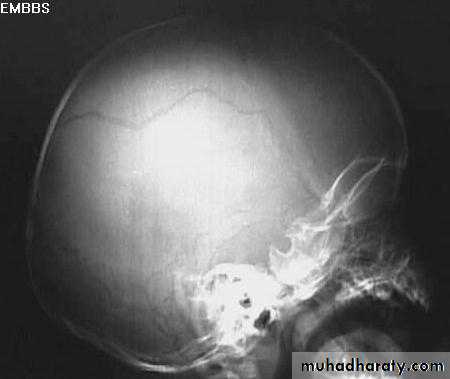

a. Plain skull x-ray

1. Can demonstrate the site and type of a skull fracture.

2. A foreign body can also be seen.

Skull Fracture

Nuro